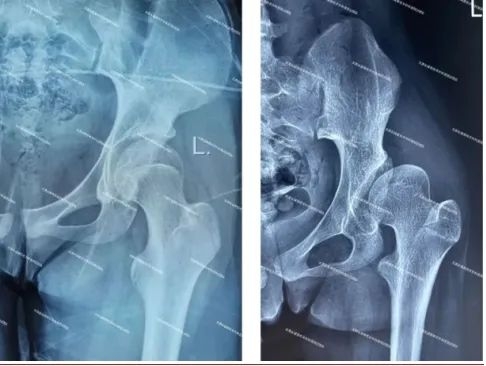

图3-4:术前影像(右侧髋关节发育不良)

(正常髋关节X线(左图)显示髋臼对股骨头的包容良好;发育不良髋关节X线(右图)显示髋臼对股骨头的包容不足。)我国人口众多,普查筛查水平相对不足,导致患者数量巨大,而疾病发现晚和处理晚。通常青少年或成人的DDH初期无明显临床症状,但随着病情进展,患者会出现髋关节周围疼痛。